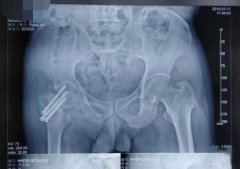

鄂州日报:我市开展首例仿生双动全髋关节置换术

鄂州市中心医院骨二科顺利完成我市首例仿生双动全髋关节置换